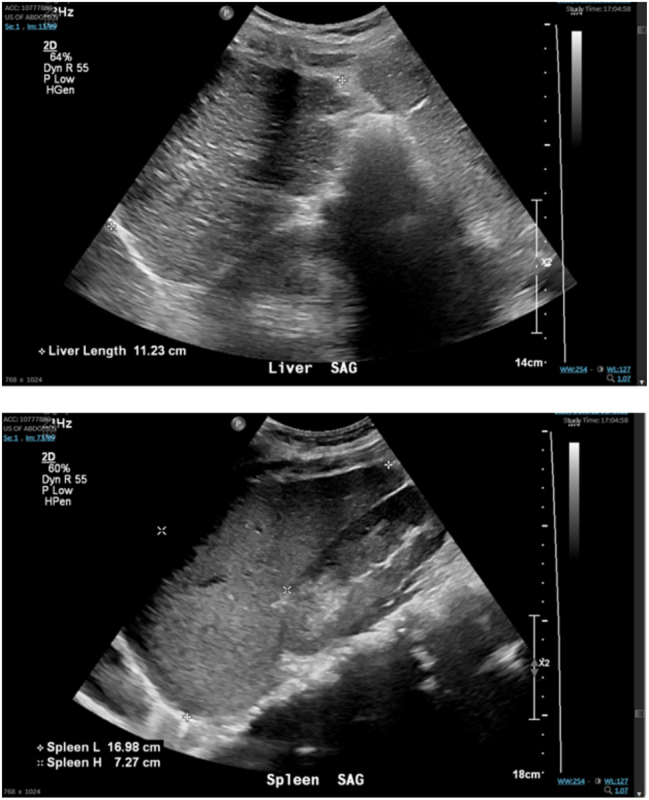

Case presentation: A 29-year-old G4P0121 female with history of spontaneous bacterial peritonitis (SBP) and severe pancytopenia secondary to AIH was found to be incidentally pregnant at 7 weeks gestation. Despite multiple blood transfusions and steroids, her pancytopenia was unresponsive to therapy. At 33 weeks, she underwent primary cesarean section for persistent category II fetal heart tracing and delivered a viable infant. Delivery was complicated by hemorrhage requiring multiple blood products. Postpartum course was complicated by sepsis secondary to urinary tract infection, and decompensated cirrhosis with hepatic encephalopathy and coagulopathy. Both fetus and mother have recovered well 3 months post-delivery.